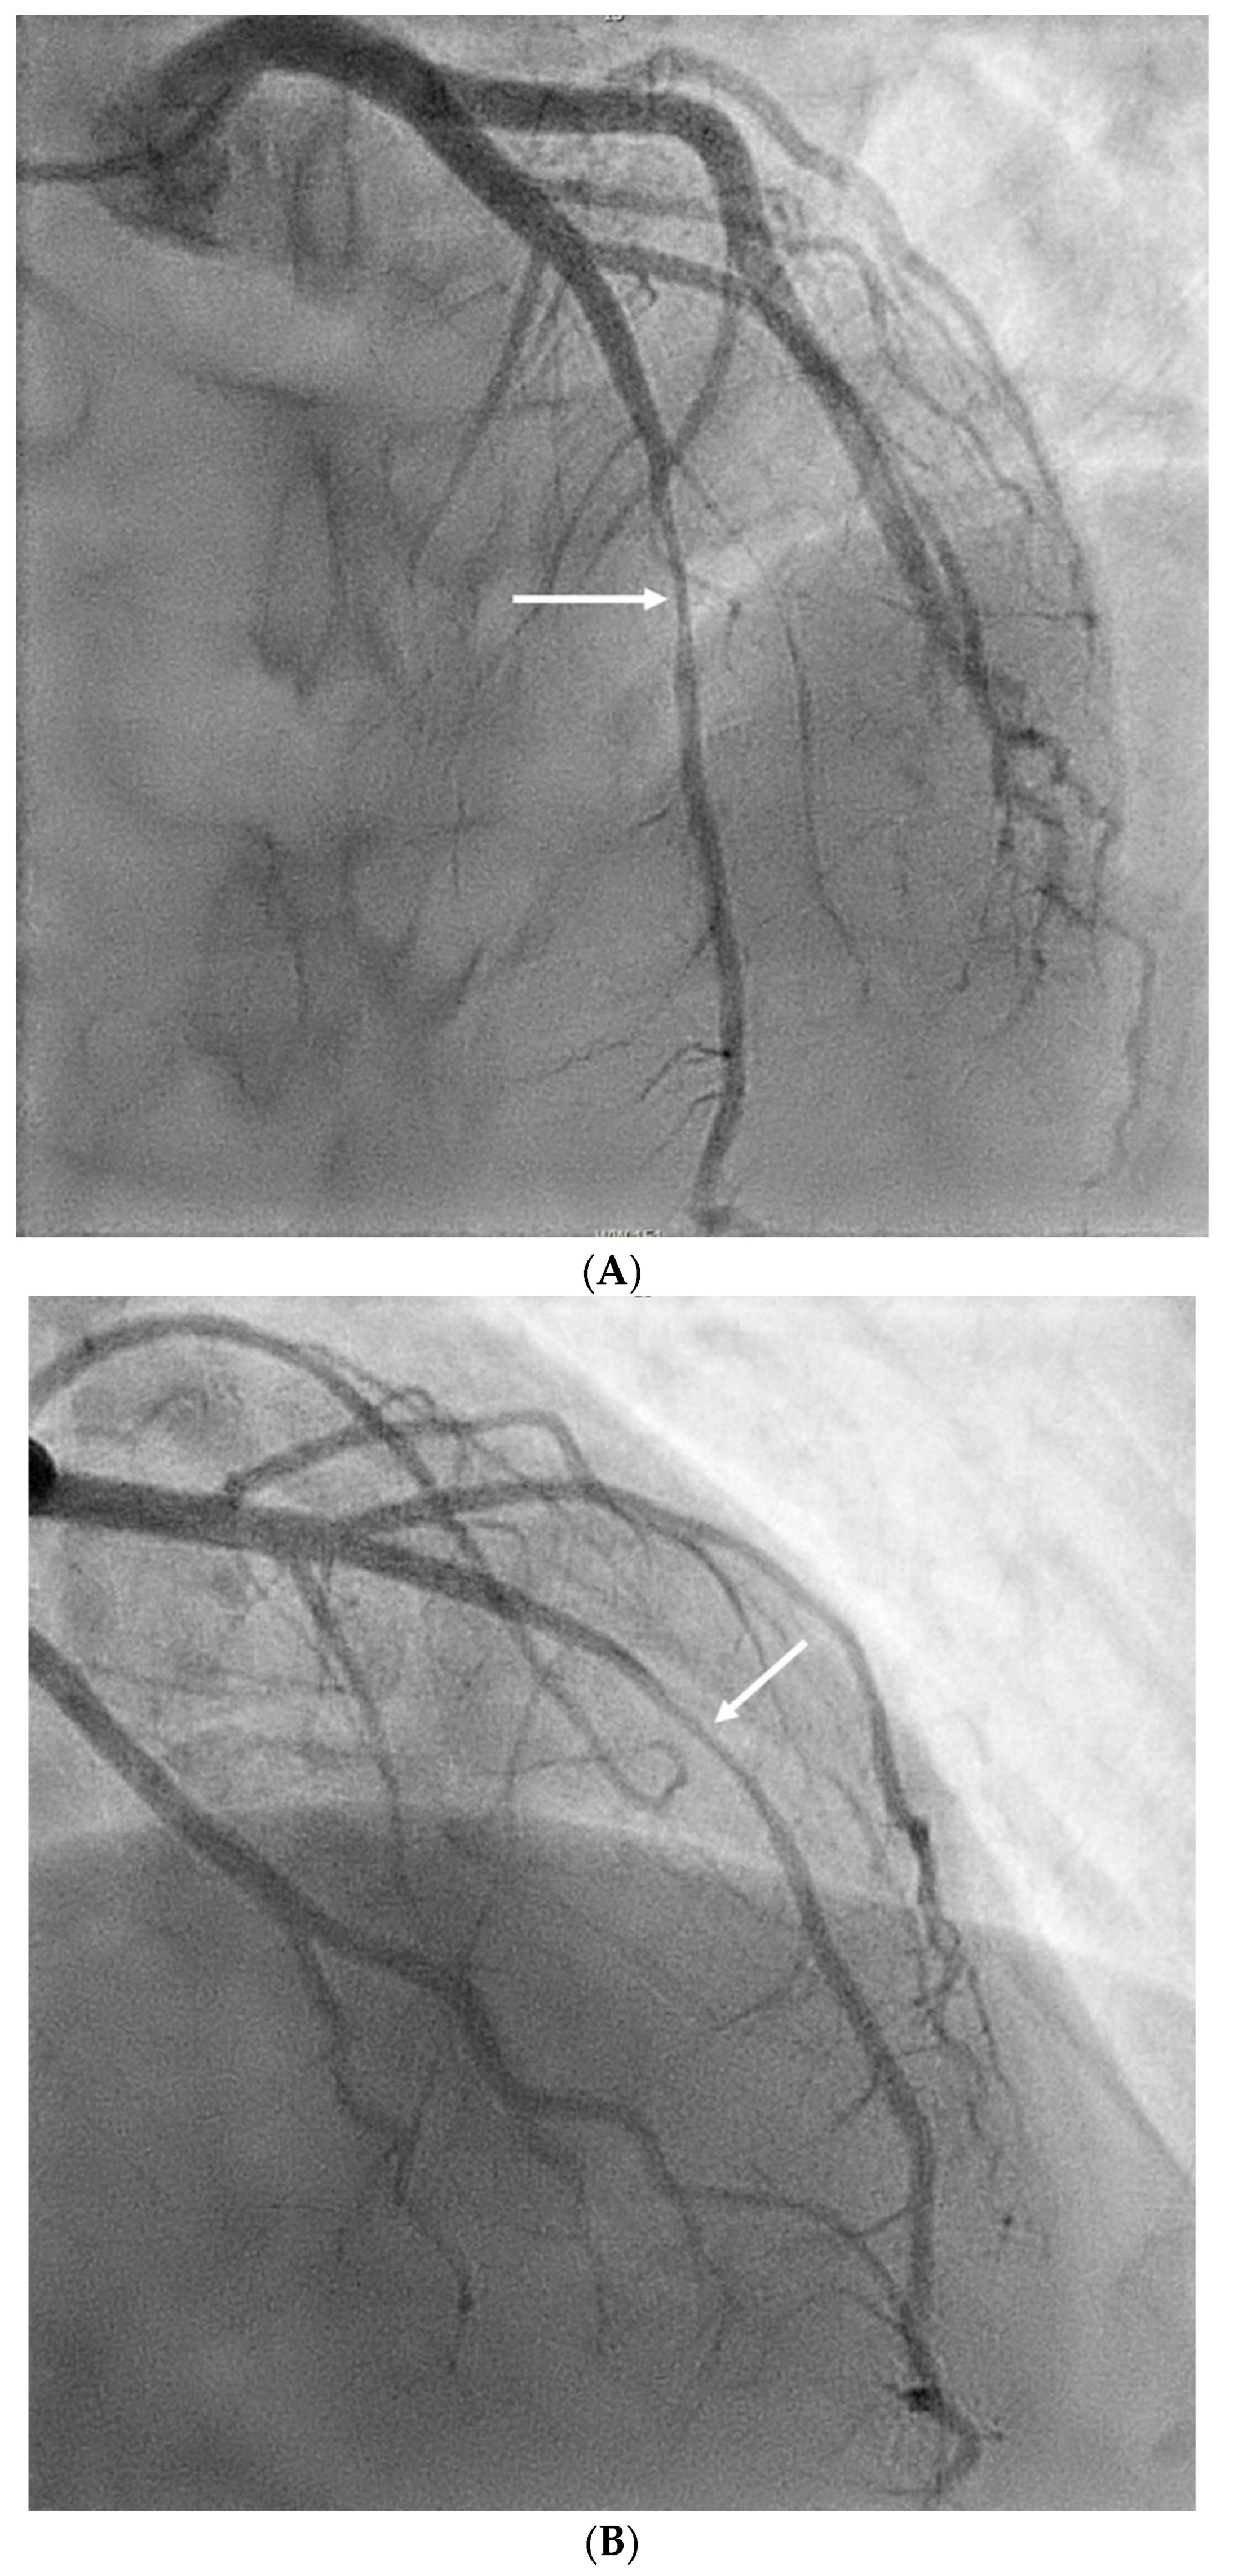

She was promptly transferred to the catheterization laboratory, where coronary angiography demonstrated a right-dominant circulation with no significant disease in the left main, circumflex, and right coronary artery. However, an 80% obstruction was detected in the mid-left anterior descending artery (LAD), unresponsive to nitroglycerin (Figure 2A,B). Given the patient’s acute presentation and recurrent asystolic episodes during the procedure, intravascular coronary imaging was not performed. The patient experienced several additional asystolic arrests during angiography, prompting the placement of a permanent pacemaker due to her otherwise normal functional status.

Figure 2. A: Coronary angiography in left anterior oblique cranial orientation with significant 80% obstruction of the mid left anterior descending artery (arrow). B: Coronary angiography in the right anterior oblique cranial orientation with the same significant ~80% obstruction in the mid left anterior descending artery (white arrow).